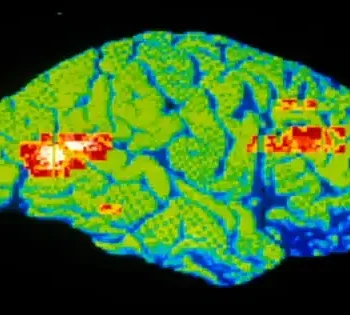

Researchers used neuroimaging and artificial intelligence to identify novel brain signatures specific to each antidepressant response. UT Southwestern University-led research has identified MRI brain imaging biomarkers that will allow for